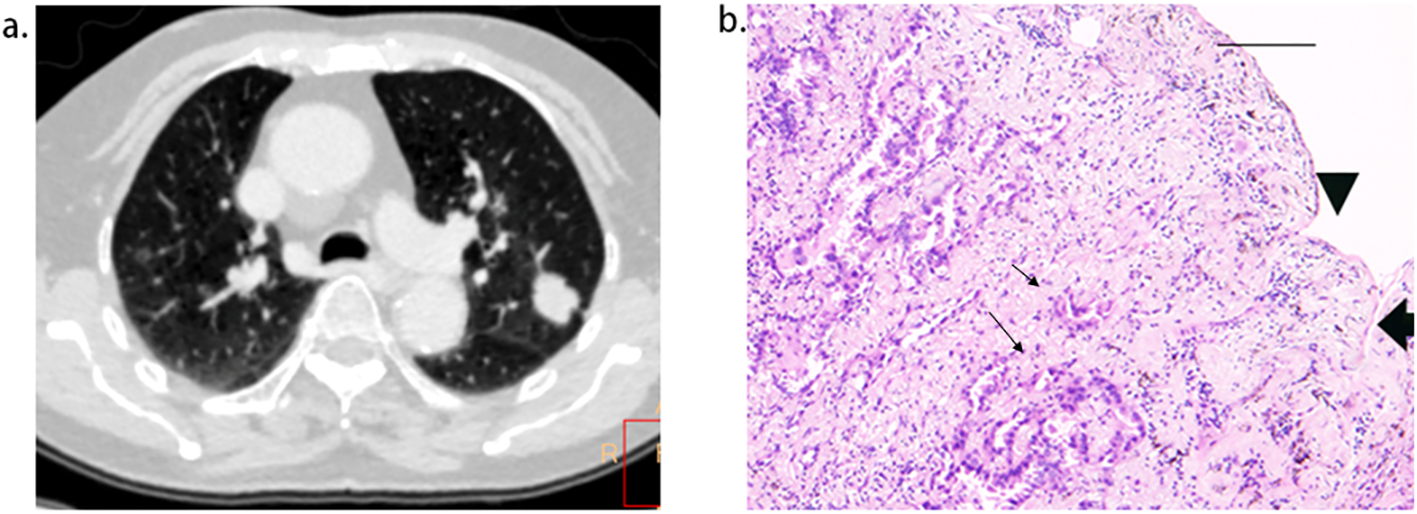

Figure 5

Short length of pleural tag (PT) was indicative of PT consisting of the pleura. (A), adenocarcinoma presenting PT with pleural indentation. (B), Scale bar = 2 mm; hematoxylin-eosin stain; magnification, X 40; Microscopic pleural indentation (arrow head) and the pleura arranged in parallel (thick arrow); Tumor cells infiltrated the pleura (thin arrow).

Tumor size was notably larger in cases with PI than in those without (26.1 mm vs. 16.8 mm), establishing it as a statistical predictor of PI in ACCs with PT. Tumor size is a well-known indicator of tumor invasiveness, as larger tumors are often associated with more invasive pathological subtypes (19), lower differentiation (21), irregular shape (22), and more frequent lymph node metastases (23). Several studies have highlighted the significance of tumor size in predicting PI in ACCs (8, 16, 24). Shi, J. et al.’s findings that larger tumor sizes are linked to PI in ACCs with PT align with our results (7). However, Hsu, J. et al.’s study, which did not find a statistical correlation between tumor size and PI in ACCs with PT (9), contrasts with our findings. This discrepancy may stem from differences in the study populations. Unlike their study, which included all types of PT, ours focused exclusively on PT with pleural indentation, typically associated with larger tumor sizes (22). Our paper also identified LPT as an independent predictor of PI in ACCs with PT. LPT, the shortest length of PT, relates closely to DLP (the distance from the lesion to the pleura). Deng, H.-Y., et al. demonstrated that NSCLCs with a DLP < 10mm are more likely to exhibit PI than those with a DLP > 10 mm (25), while Qi, L., et al. found similar outcomes for DLP < 5 mm (10). However, these studies primarily focused on tumors in direct contact with the pleura, and to the best of our knowledge, few have concentrated on tumors without pleural contact. Papillary/acinar subtype ACCs have been observed to have a smaller distance from the invasive component to the pleura than the alveoli/lepidic subtype (26), suggesting that a short DLP is associated with tumor invasiveness. Additionally, the resistance of adjacent inflated lung tissues gradually limits the movement of the retracted pleura toward tumors (13, 27, 28), resulting in short, parallel arrangements of pleura on the tumor side (Figure 5). Conversely, the extension of interlobular septa and fibrosis faces fewer restrictions. Therefore, a small LPT indicates that PT primarily consists of pleura and is partially associated with tumor invasiveness. An LPT < 3mm demonstrated a high sensitivity of 96.9% for predicting PI, supporting its utility in predetermining PI in this study. Additionally, our study found that multiple PTs to multiple types of pleura was independent predictor for PI, correspondent with Q, S., et al.’s recent work (20), in which the sensitivity and specificity were 11%, 98%, respectively. The underline explanation for this statistical significance was not merely more pleural contact sites increasing the possibility of pleural invasion, because previous investigations did not reveal multiple PTs involving single pleura correlated with PI (13, 27). A higher invasiveness to infiltrate in more directions maybe the additive interpretation. The combined use of tumor size, LPT, and multiple PTs to multiple types of pleura slightly improved predictive efficiency for PI, achieving higher accuracy and AUC. However, the low sensitivity and moderate accuracy of prediction still existed and align with previous reports (9, 29).